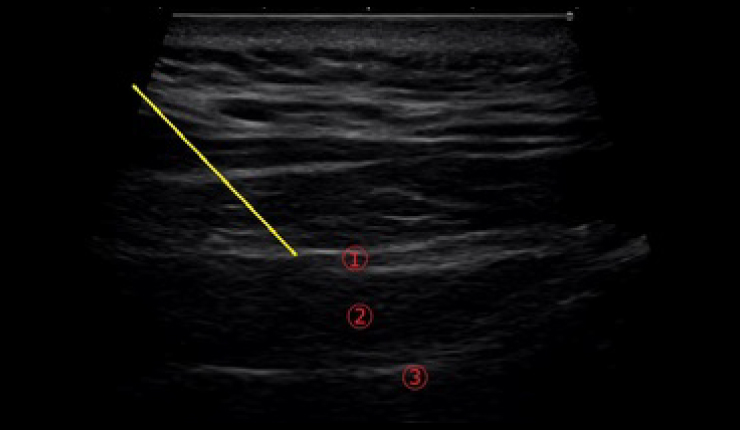

頻度の多い片頭痛を予防するために大後頭神経ブロック、星状神経節ブロックを行います。神経ブロック注射は専門的な知識と高度な技術を要するので、限られた施設でのみ行われています。慢性片頭痛の方に後頭神経ブロックを行うことで血中のCGRP濃度が低下するという報告があります(Neurol Int. 2022 Mar; 14(1): 199-206.)。当院では超音波を用いて大後頭神経ブロック注射を行っています。可視化してブロック注射を行うことで高い安全性と確実性が期待できます。

後頭神経図 黄色:注射針 ①:大後頭神経 ②:下頭斜筋 ③:頚椎